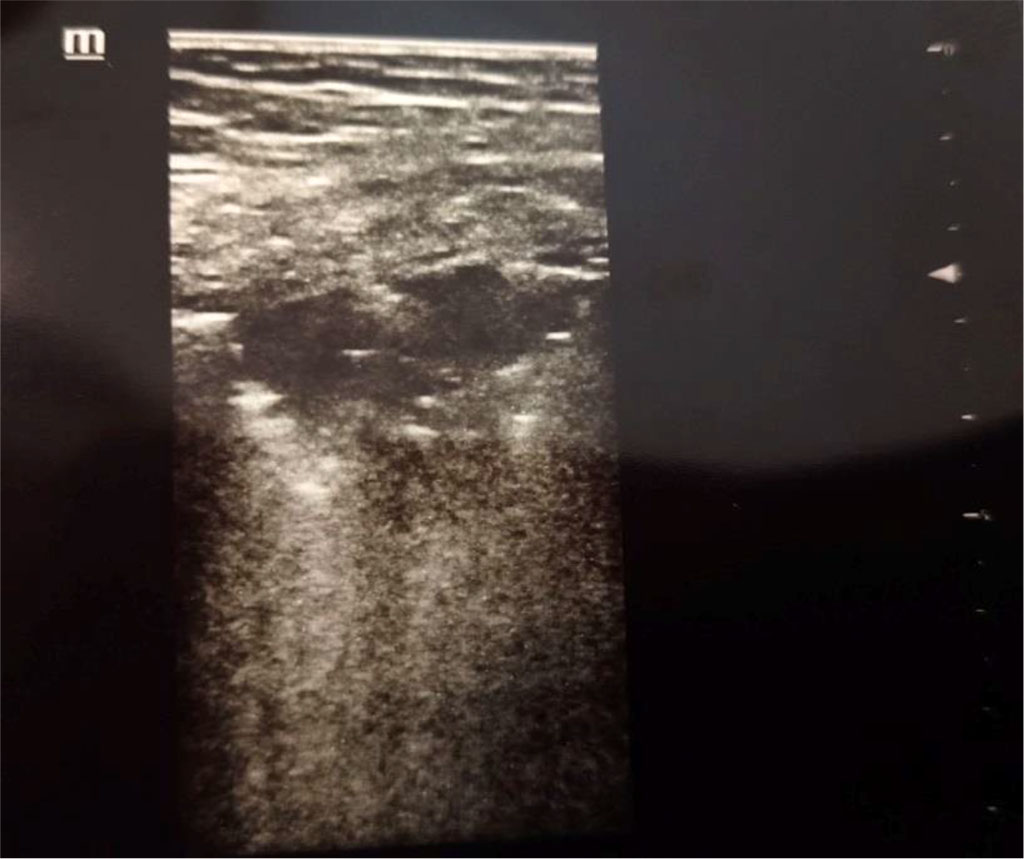

Figure 1. Consolidation. Author’s private materials.